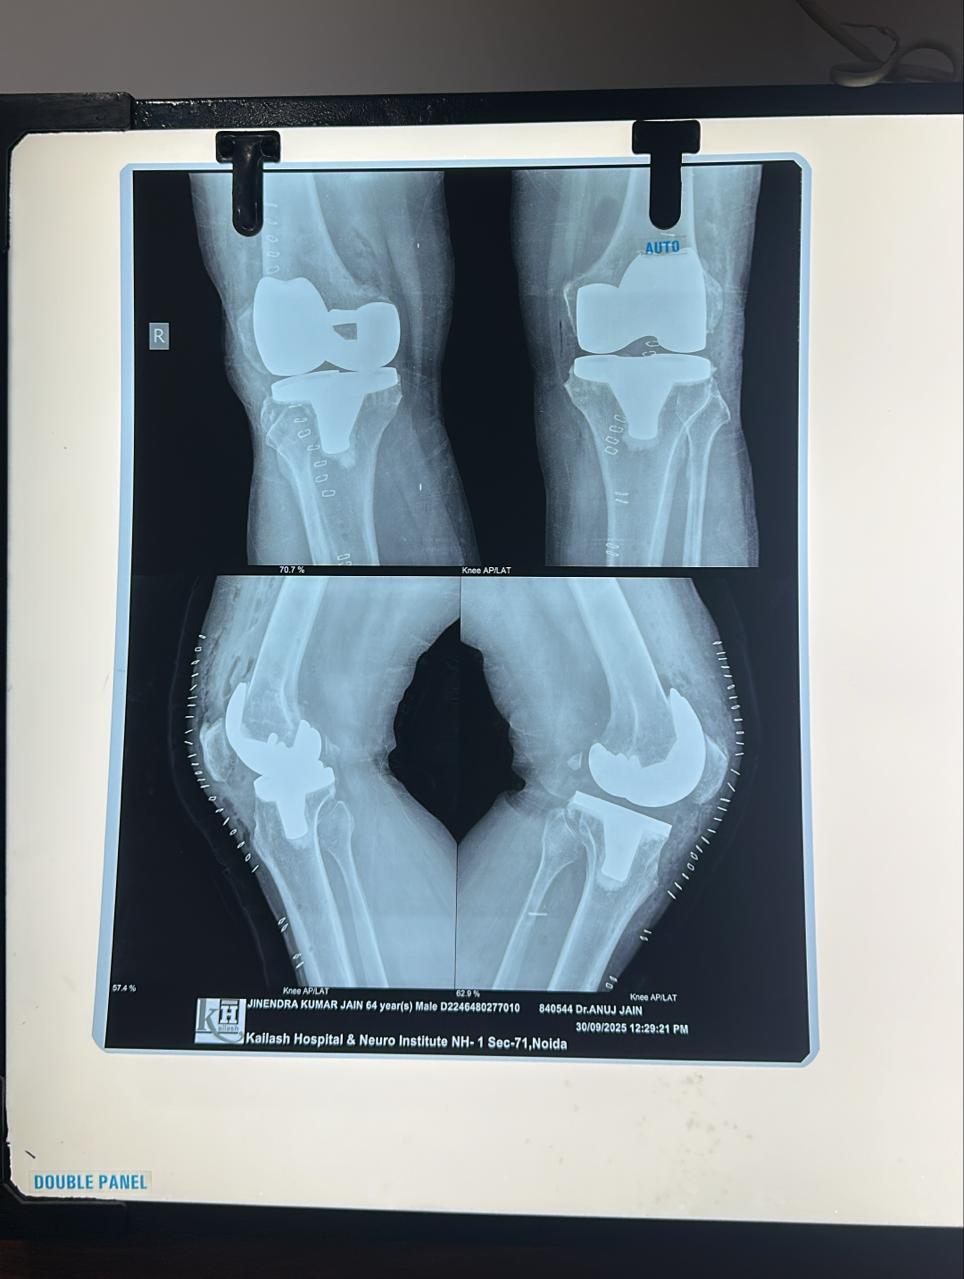

Postoperative X-ray Findings

The postoperative X-rays show:

- Perfectly aligned femoral and tibial components

- Symmetrical implant positioning on both knees

- Corrected varus deformity

- Stable, secure prosthesis with balanced joint spacing

These images reflect the accuracy achievable through Bilateral Robotic Total Knee Replacement.